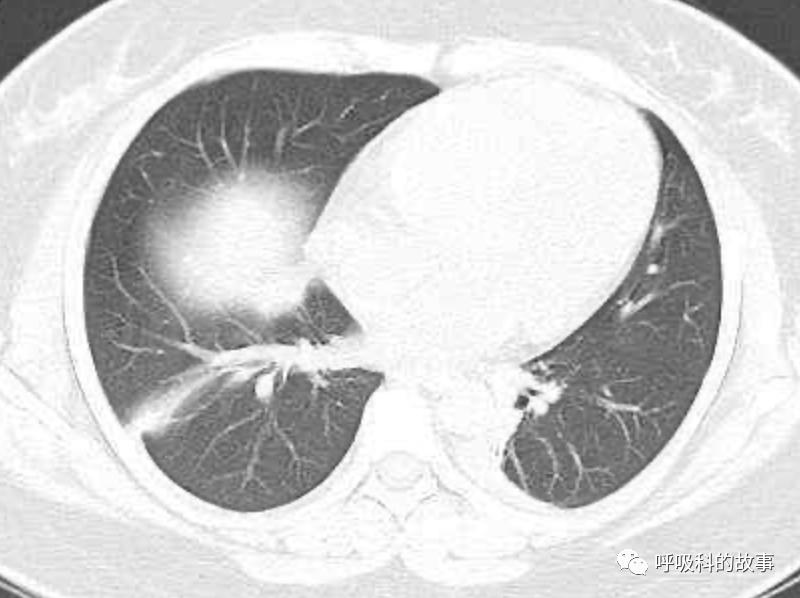

可是在6月26日(往院第18天)仍持续发热的情况下复查肺部CT,肺部病灶已明显吸收了。那么患者发热的原因到底是什么呢?为什么患者高热的情况下血白细胞不升反降,C反应蛋白也没有明显增高?这个时候消化科医生也迷茫了,这可怎么办?于是请感染科和呼吸科医生一起会诊,共商计策。